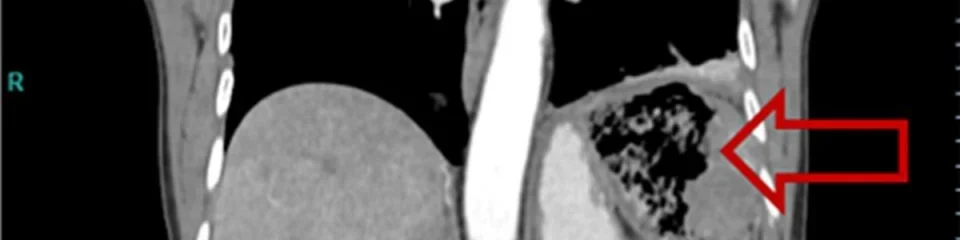

Em um caso inusitado relatado na revista científica Cureus Medical Jornal em julho deste ano, médicos retiraram um pedaço de curativo que estava há mais de 20 anos no intestino de uma mulher de 65 anos. Segundo a publicação, a paciente chegou ao pronto-socorro com fortes dores abdominais, febre e inchaço no membro inferior direito. Ela também vinha apresentando sintomas de anorexia há um mês e perdeu cerca de oito quilos no período.Em exames realizados durante o atendimento emergencial, a mulher foi diagnosticada com anemia e início de processo inflamatório na região do abdômen. A paciente fez uma ultrassonografia, e os médicos encontraram a fonte do problema: um corpo estranho alojado em sua cavidade abdominal.Os responsáveis pelo caso acreditam que a gaze tenha sido esquecida durante uma cirurgia feita em 1999 para retirada de um câncer da mucosa gástrica. Os médicos revisaram todos os exames realizados pela paciente ao longo dos últimos 20 anos para determinar quando o curativo começou a aparecer nas imagens.A presença de uma massa localizada no quadrante superior esquerdo do abdômen já tinha sido mencionada nos laudos. “Porém, a paciente desconhecia essa informação porque os exames nunca tinham sido abertos ou analisados por nenhum médico”, contam os especialistas, na publicação.De acordo o artigo, a incidência de material cirúrgico esquecido na cavidade abdominal é baixa, na ordem de uma em cada mil a 1,5 mil intervenções. Porém, este caso apresentou uma novidade, já que a paciente permaneceu completamente assintomática por mais de 20 anos com a presença de um corpo estranho consideravelmente grande na cavidade abdominal.Receba notícias do Metrópoles no seu Telegram e fique por dentro de tudo! Basta acessar o canal: https://t.me/metropolesurgente.Já leu todas as notas e reportagens de Saúde hoje? Clique aqui.Fonte: Metrópoles